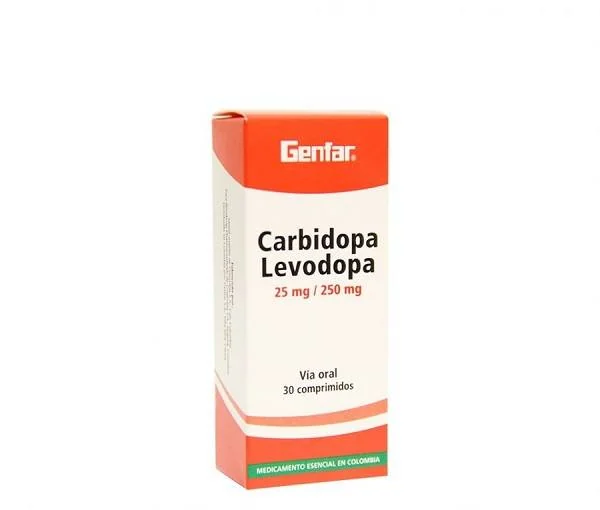

کاربیدوپا_ لوودوپا. این دارو می تواند سطح دوپامین انتقال دهنده عصبی را افزایش دهد .